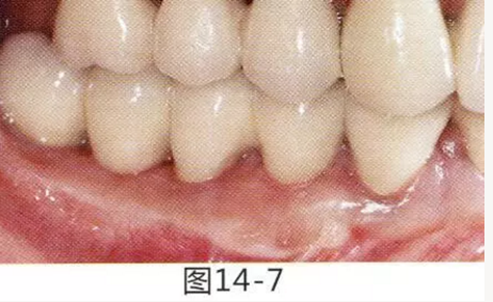

圖14-1 修復體周圍角化牙齦較少,很難進行清潔的狀態(tài),并有緣下齲壞的發(fā)生。

圖14-2,3 徹底去除齲壞后,試圖通過游離齦移植獲取生物學寬度和附著齦。

圖14-4~6修復體周圍角化牙齦較少,很難進行清潔的狀態(tài),并有緣下齲壞的發(fā)生。

圖14-7 配戴最終修復體完成5年后的狀態(tài)。保持良好。